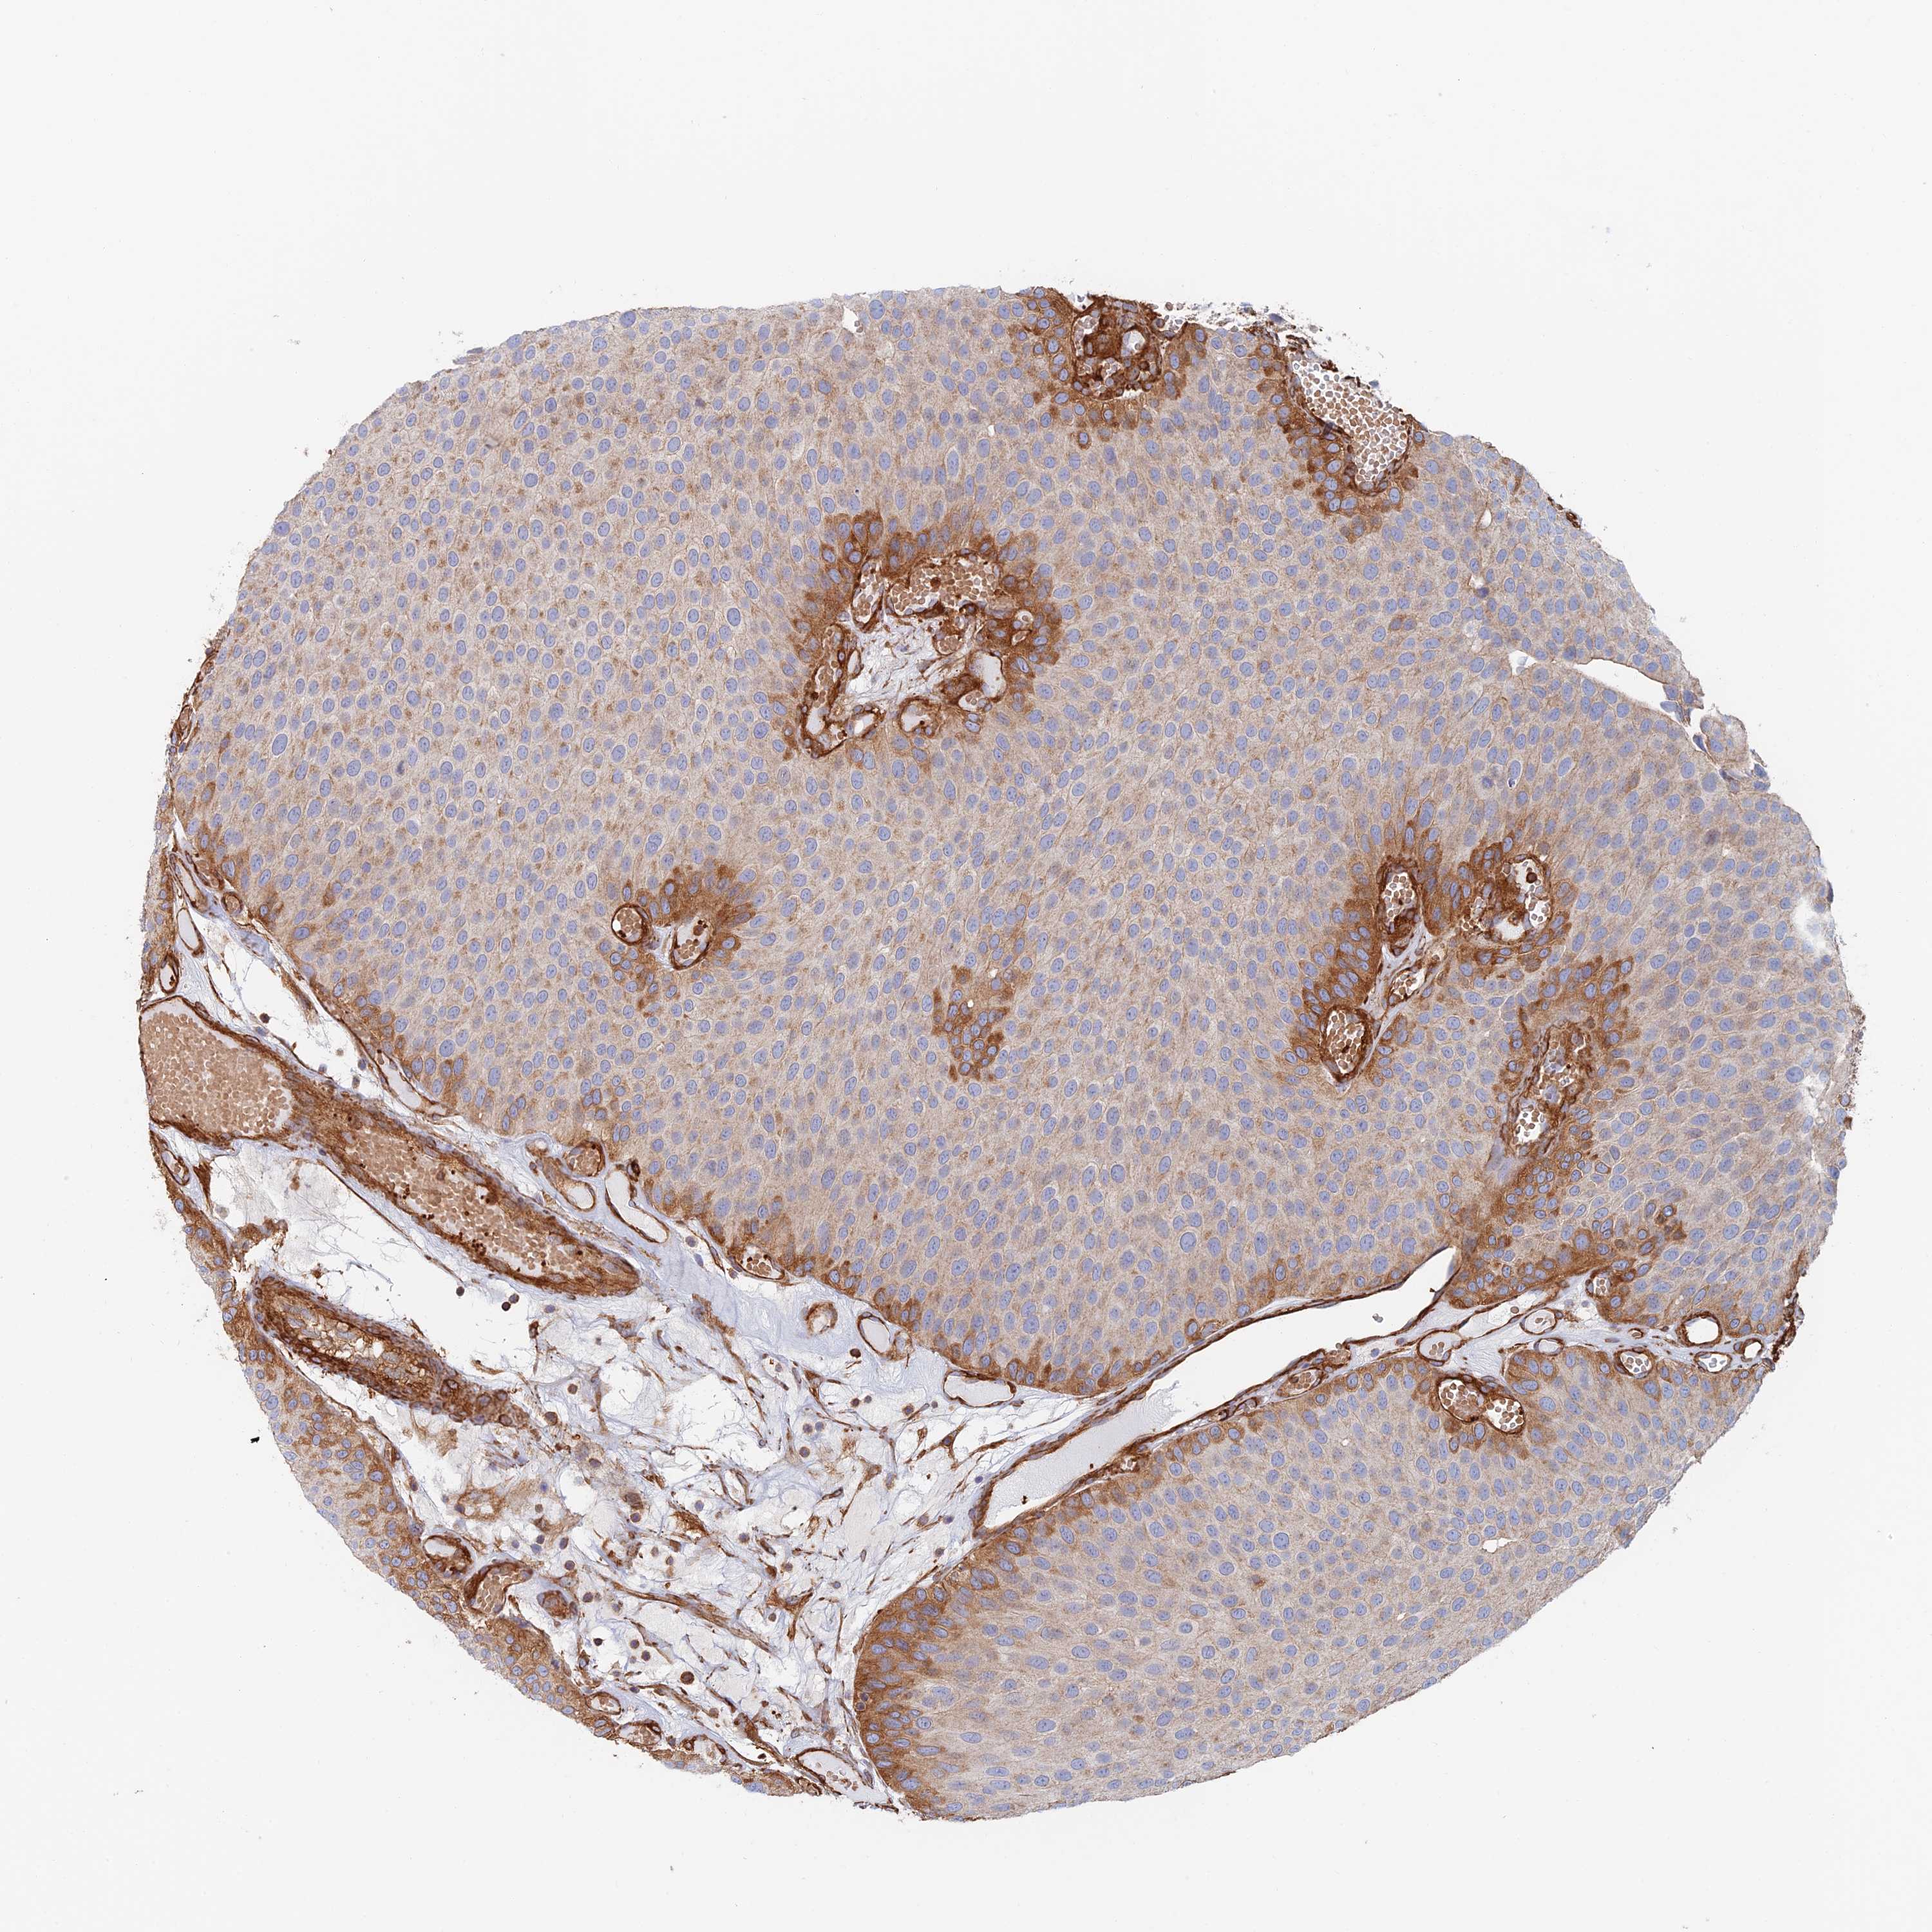

UROTHELIAL CANCER - Protein expressioni

A mouse-over function shows sample information and annotation data. Click on an image to view it in a full screen mode. Samples can be filtered based on level of antibody staining by selecting one or several of the following categories: high, medium, low and not detected. The assay and annotation is described here.

Antibody stainingi

Antibody staining in the annotated cell types in the current human tissue is reported as not detected, low, medium, or high, based on conventional immunohistochemistry profiling in selected tissues. This score is based on the combination of the staining intensity and fraction of stained cells.

Each image is clickable and will lead to virtual microscopy that enables deeper exploration of all samples and also displays staining intensity scores, fraction scores and subcellular localization as well as patient and tissue information for each sample.

Antibody CAB025747

Antibody CAB044670

Staining

High

Medium

Low

Not detected

Intensity

Strong

Moderate

Weak

Negative

Quantity

>75%

75%-25%

<25%

None

Location

Nuclear

Cytoplasmic/membranous

Cytoplasmic/membranous,nuclear

Urothelial carcinoma, Low grade

Urothelial carcinoma, High grade